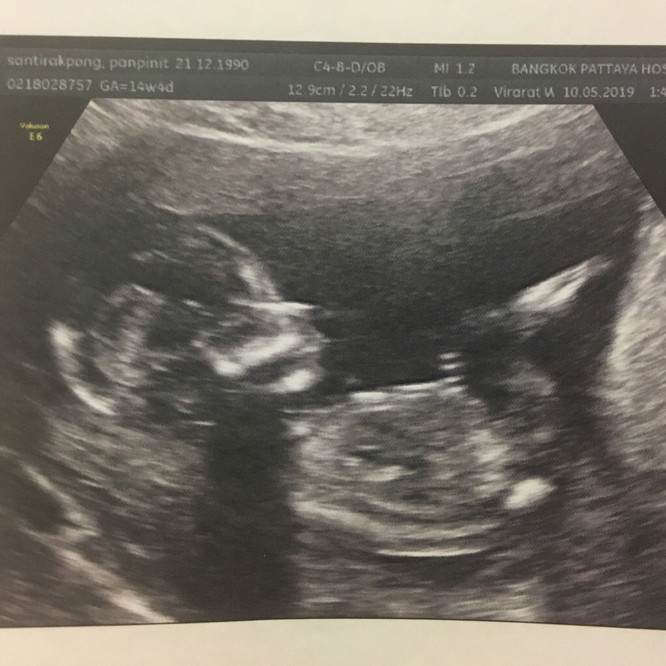

13weeks5dayspregnant ค่ะ ตอนนี้ 22week+ แล้วอยากเห็นลูกอีกจัง

13w ค่ะ ทำท่าเหมือนจะดูดนิ้วเลยค่ะ 🥰